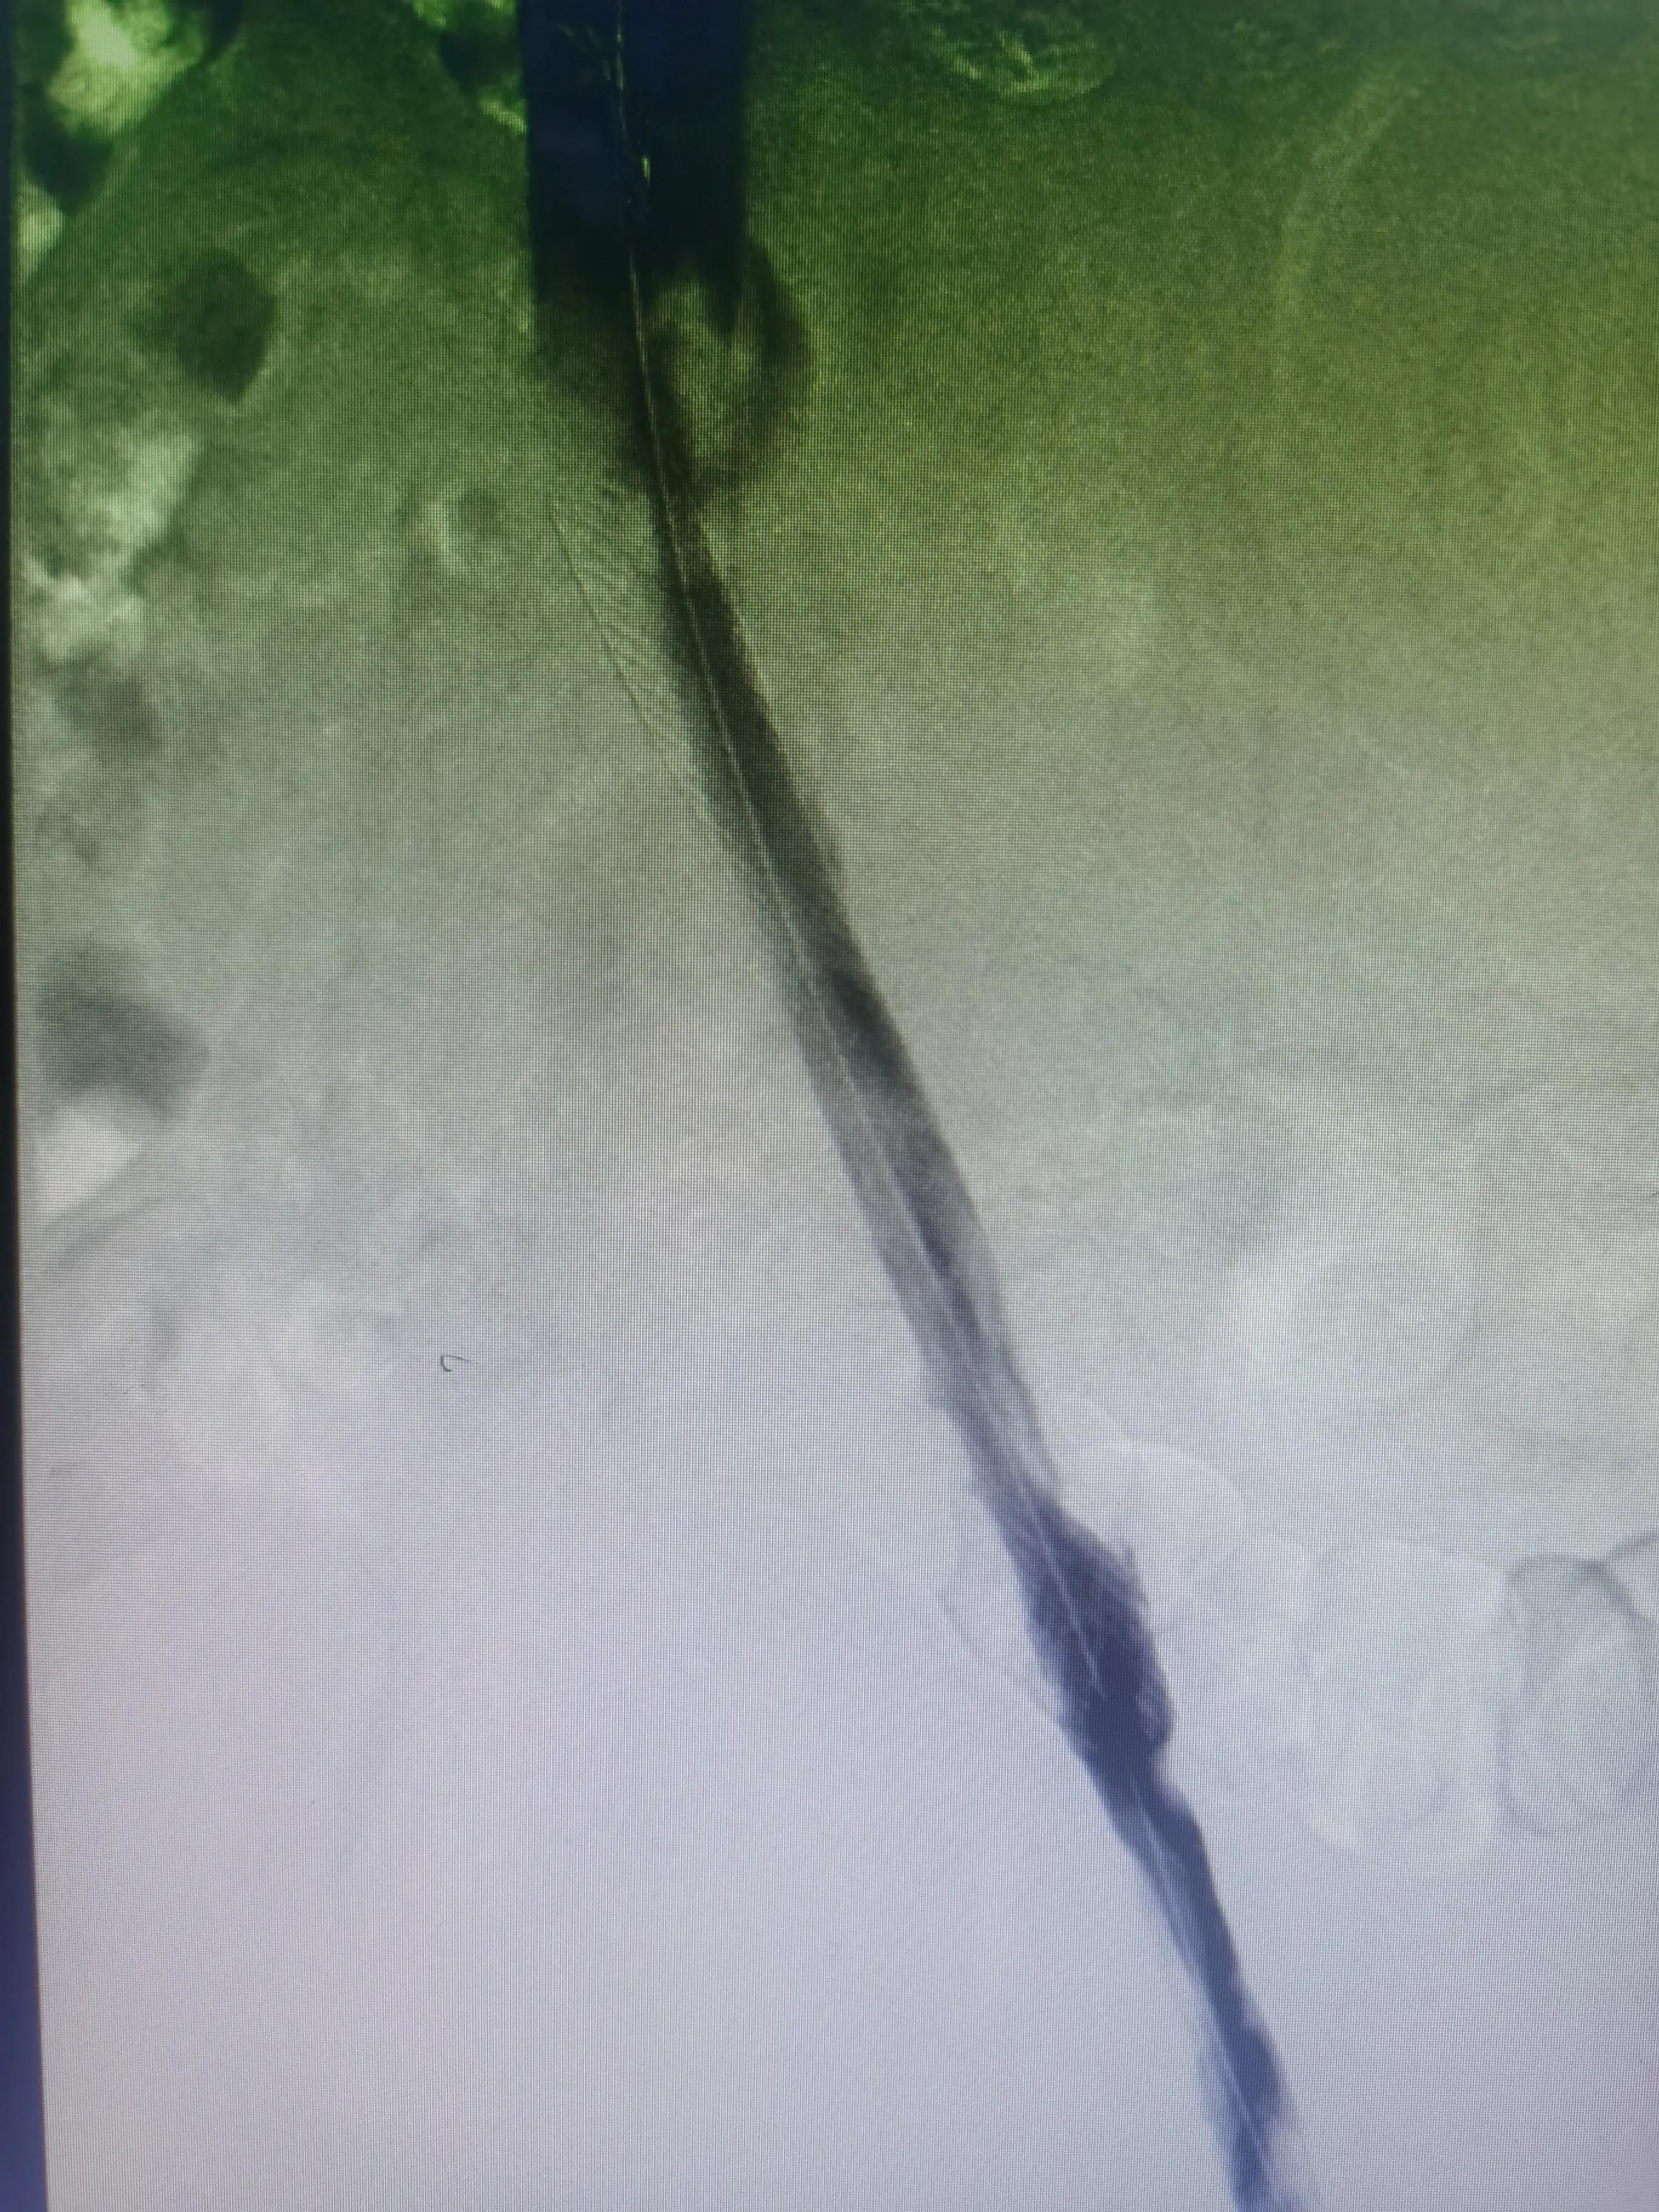

支架后髂静脉通畅

术前髂静脉闭塞

下腔静脉滤器网住血栓

支架植入后血流通畅